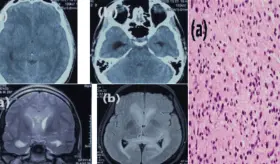

Los estudios de neuroimagen mostraron un patrón atípico de hiperintensidades simétricas en la sustancia blanca, sin realce con contraste ni restricción en la difusión, hallazgos poco comunes para un tumor cerebral.

El tumor mostró un comportamiento clínico agresivo, con crecimiento rápido, recurrencia temprana postquirúrgica y desenlace fatal, asociado a características histológicas de mal pronóstico.